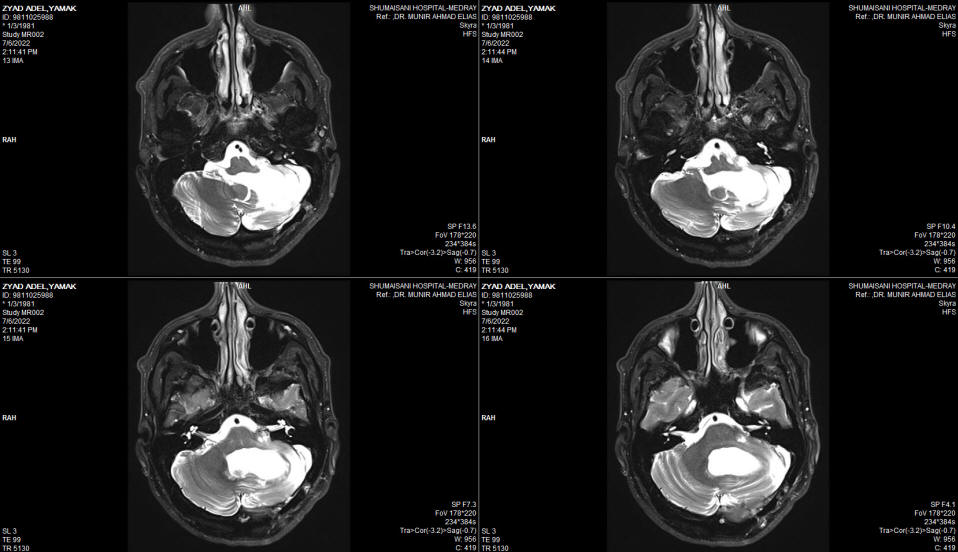

The patient then came 26-June-2002 complaining of double vision, complete hearing loss left side, but he walk without aid with almost complete recover of the left facial nerve. Still complaining of swallowing difficulty, but he mention that the assort of the eating food is widening, but still using PEG.  MRI of the brain done 06-July-2022 showing massive malacia of the left cerebellar hemisphere. The brain stem and the posterior circulation are intact. The MRV showing absent left transverse sinus , which could be a variant. The left trigeminal nerve is not compressed and the canal is wide.

Fig:-3 Severe malacia and atrophy of the left cerebellar hemisphere with preserved brainstem.